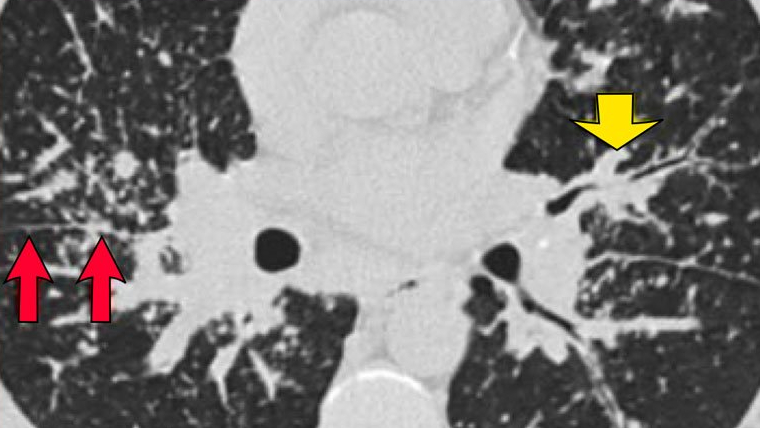

Cụ thể hơn, trong trường hợp bệnh nhân mắc viêm tiểu phế quản hô hấp, chúng ta sẽ quan sát được các nốt có độ mờ kính chiếm ưu thế ở thùy trên trên hình chụp HRCT. Bên cạnh đó, cũng quan sát được dấu hiệu dày thành phế quản. Tiểu thùy thứ cấp có xuất hiện bẫy không khí.

Một số dấu hiệu bất thường thể hiện trên hình ảnh HRCT khi bệnh nhân mắc các bệnh lý này như: